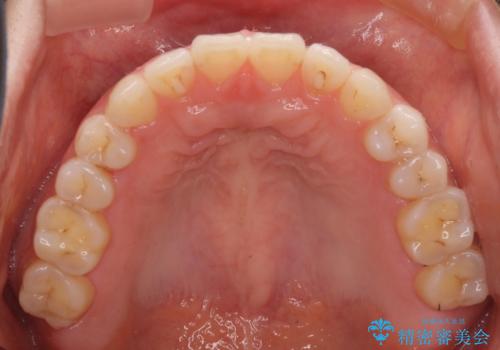

- 上下の前歯の隙間を気にして来院された患者様です。

インビザラインを用い、上下歯列のスペースを閉じていくこととしました。

治療期間中は奥歯がほとんど咬めない状態が続き、食事に大変苦労されました。

最終的には隙間もしっかりと閉じ、奥歯も咬みやすい状態でしあげることができました。